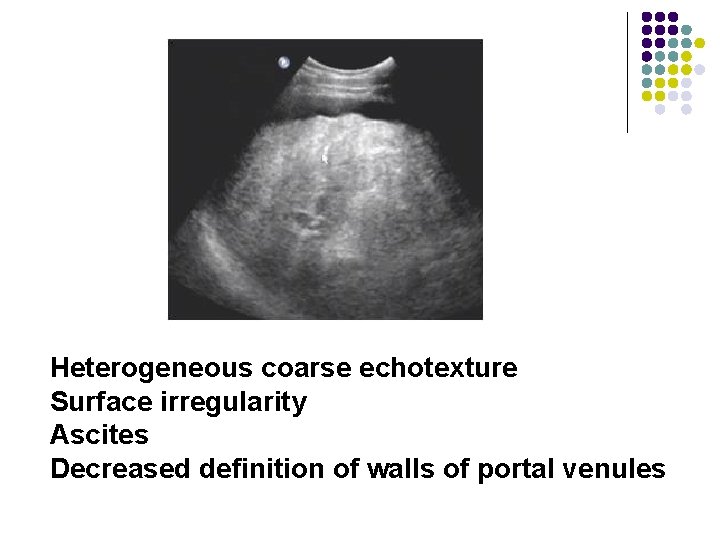

Hepatic Cirrhosis l l Surface irregularity Increased echogenicity Heterogeneous coarse echotexture Ascites

Heterogeneous coarse echotexture Surface irregularity Ascites Decreased definition of walls of portal venules

Heterogeneous coarse echotexture Surface irregularity Ascites Decreased definition of walls of portal venules